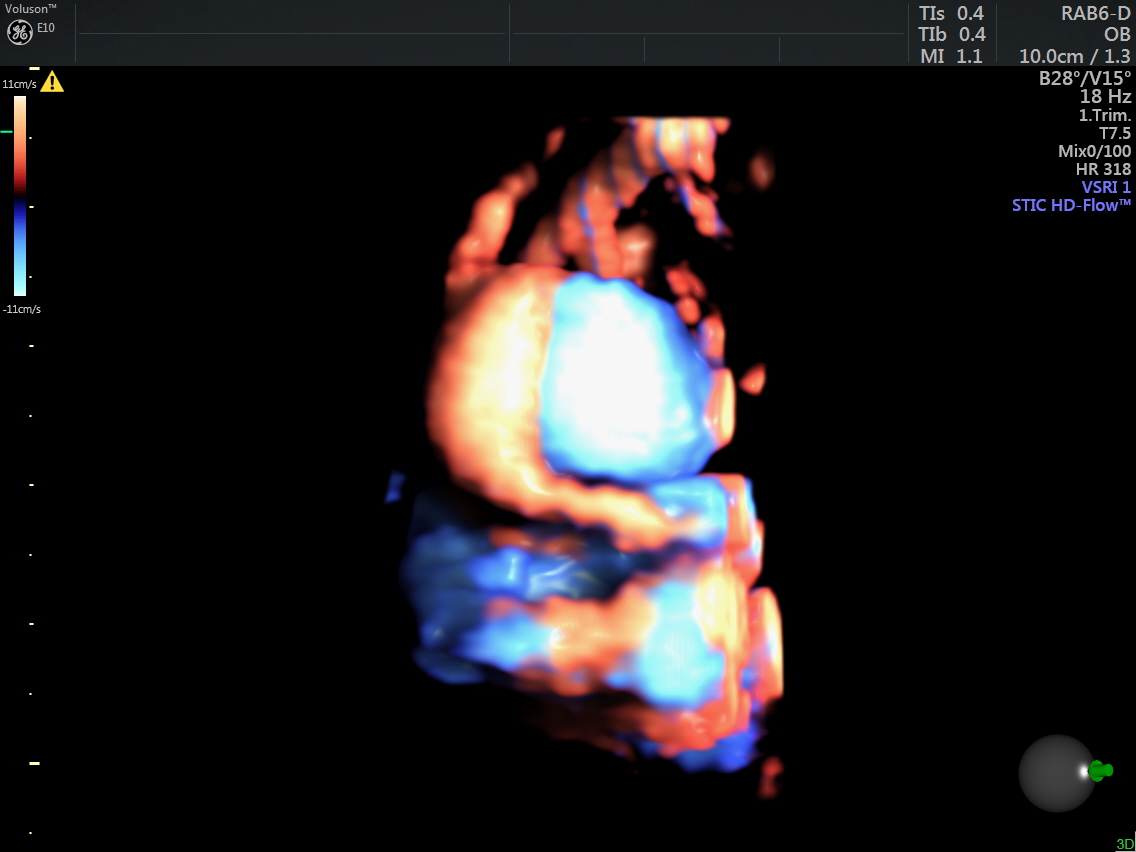

STIC HIGH DEFINITION FLOW reconstruction images also show a feeding vessel and a vessel leaving the vascular structure,